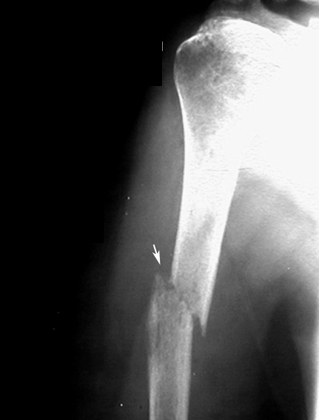

Pathological fracture

Bone Metastasis

Lytic lesion of humerus with a pathological fracture.

• Primary Cancer lung.